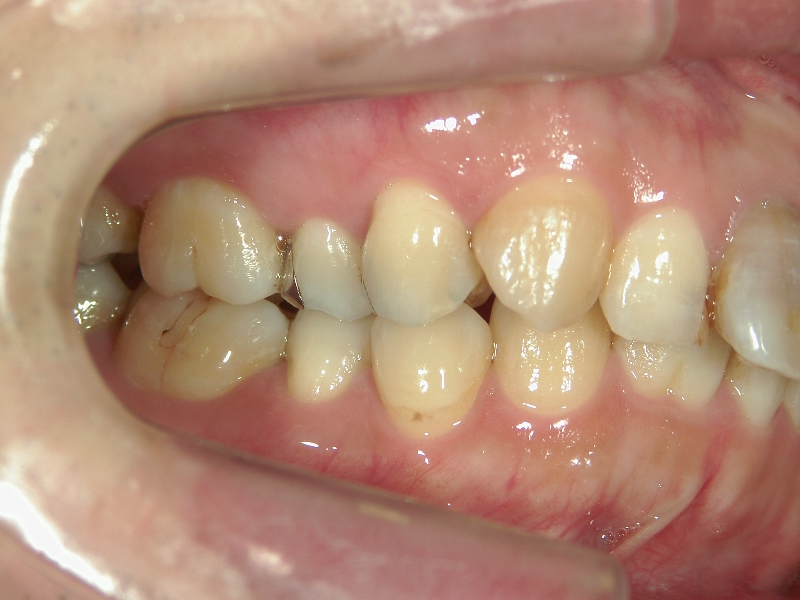

33歳男性 浜松市東区在住

治療期間1年7ヶ月

主訴:前歯の歯並びが気になる。

矯正歯科 治療前 上顎の左右4番計2本を抜歯し叢生を改善。